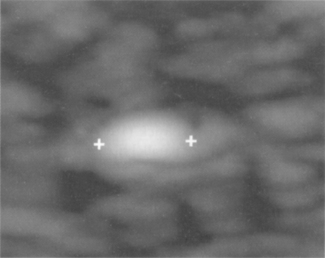

For meaningful and comparative assessments, this test is performed using exactly the same settings for a given transducer. These are normally performed using a test phantom with the machine operating at maximum output power and using a deep focal zone setting to obtain a measurement of the maximum penetration depth. Figure 13.10 shows a typical image using the recommended set-up to test the penetration depth. The maximum depth at which scattering echoes can be detected and differentiated from background electronic noise is determined and measured using the electronic calipers.

image

Fig. 13.10 Measurement of penetration depth. Electronic caliper indicates the maximum penetration depth determined by the operator